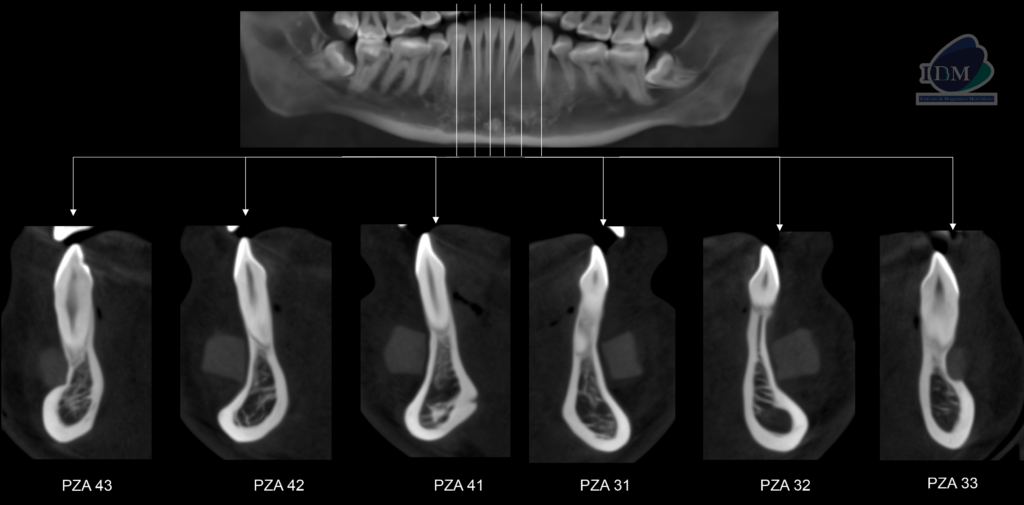

A la evaluación de la tomografía volumétrica (cone beam) en los cortes axiales (Figura 2) y transaxiales (Figura 3) se observó como hallazgo incidental la presencia de una imagen isodensa homogénea, limites definidos a nivel de la zona media de maxilar inferior, que se extendía desde pieza 33 a 43 que ocasionaba un defecto óseo en tabla vestibular de zona de piezas 33 y 43.

CORTES TRANSAXIALES